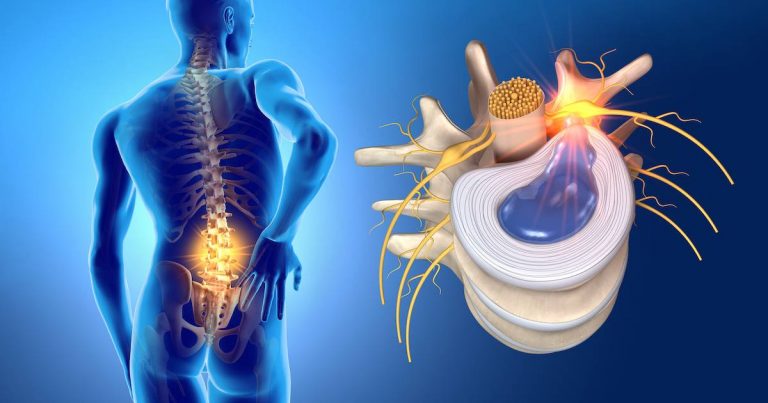

آرتروز گردن یک آسیبشناسی دژنراتیو است که بر مهرههای گردن تأثیر میگذارد. مانند هر فرایند آرتروز، به دلیل کشش بیش از حد عضلانی است که باعث میشود غضروف شروع به ساییدگی کند و دیسک بین مهرهای را تغییر شکل دهد. کسانی که از این آسیب آرتروز رنج میبرند مشکلاتی...